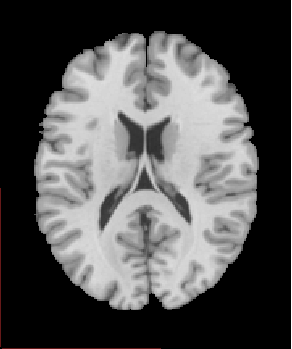

1-2 Imagerie Anatomique

1-2-1 Anatomie Généralités

Images Anatomie Généralités

Sujet1211sansscalp.PNG